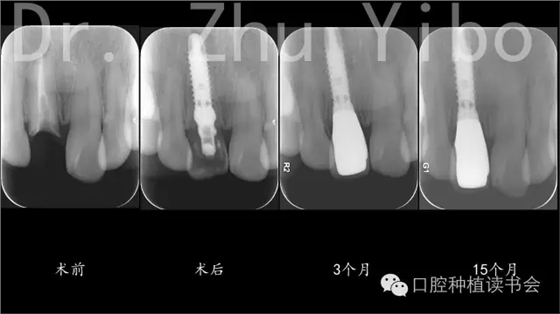

1、采用種植微動力系統(tǒng),微創(chuàng)拔除腭側牙根,保留部分唇側牙根,按照最終修復體的最佳位置進行常規(guī)種植窩洞制備(圖2)。

2、植入種植體,種植體軸向穿出點為修復后牙冠切端偏舌側,深度為唇側齦緣下3mm,緊貼唇側牙根,距離鄰牙大于1.5mm,植入初期穩(wěn)定性大于35Ncm(圖3)。

5、術后拍根尖片,確認臨時冠就位良好(圖12)。

8、戴最終修復體,就位良好(圖12)。 術后1年復查,牙冠完好,牙齦美學評分14分(圖10、11)。